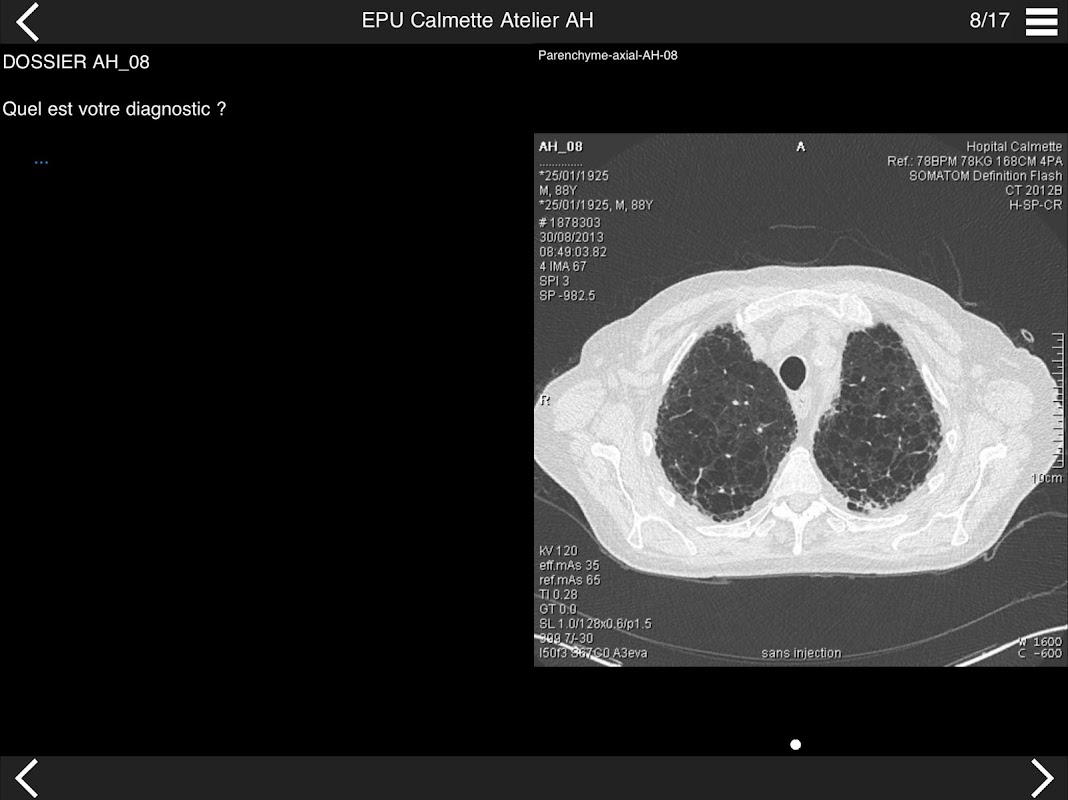

Retrouvez les cas cliniques du Cours intensif de TDM multicoupe du thorax dans cette application.

* BPCO et nodules pulmonaires : recommandations en 2017

* Pathologie interstitielle : lésions élémentaires et « patterns »

* Pathologie vasculaire et médiastinale